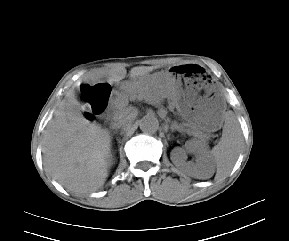

标题: CT19533:病变来源于哪?

患者,男,发现上腹部包块两月余。

病变位于肝胃间隙,实际就是位于小网膜囊(左肝下后间隙),呈轻度不均匀性强化,腹腔内及腹膜后见多发肿大淋巴结。所以我考虑肝胃间隙恶性胃肠间质瘤并淋巴结转移。

病灶强化不显著,灶周及腹膜后见多量淋巴结肿大,考虑淋巴瘤可能,其次考虑间质瘤

病灶与胰腺分界不清,来源于胰腺?

强化后病变与胃壁分界清楚,并且血供不是来源胃壁血管。考虑胰腺颈体癌并腹腔腹膜后淋巴结转移。

肝胃韧带内及腹膜后可见多发增大的淋巴结影,首先考虑转移.